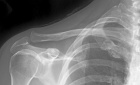

65 year old male had a lesion removed from his right supraclavicular area at an outside facility, suspected to be a lymph node.

Zoom image: Radiological image Radiological image.